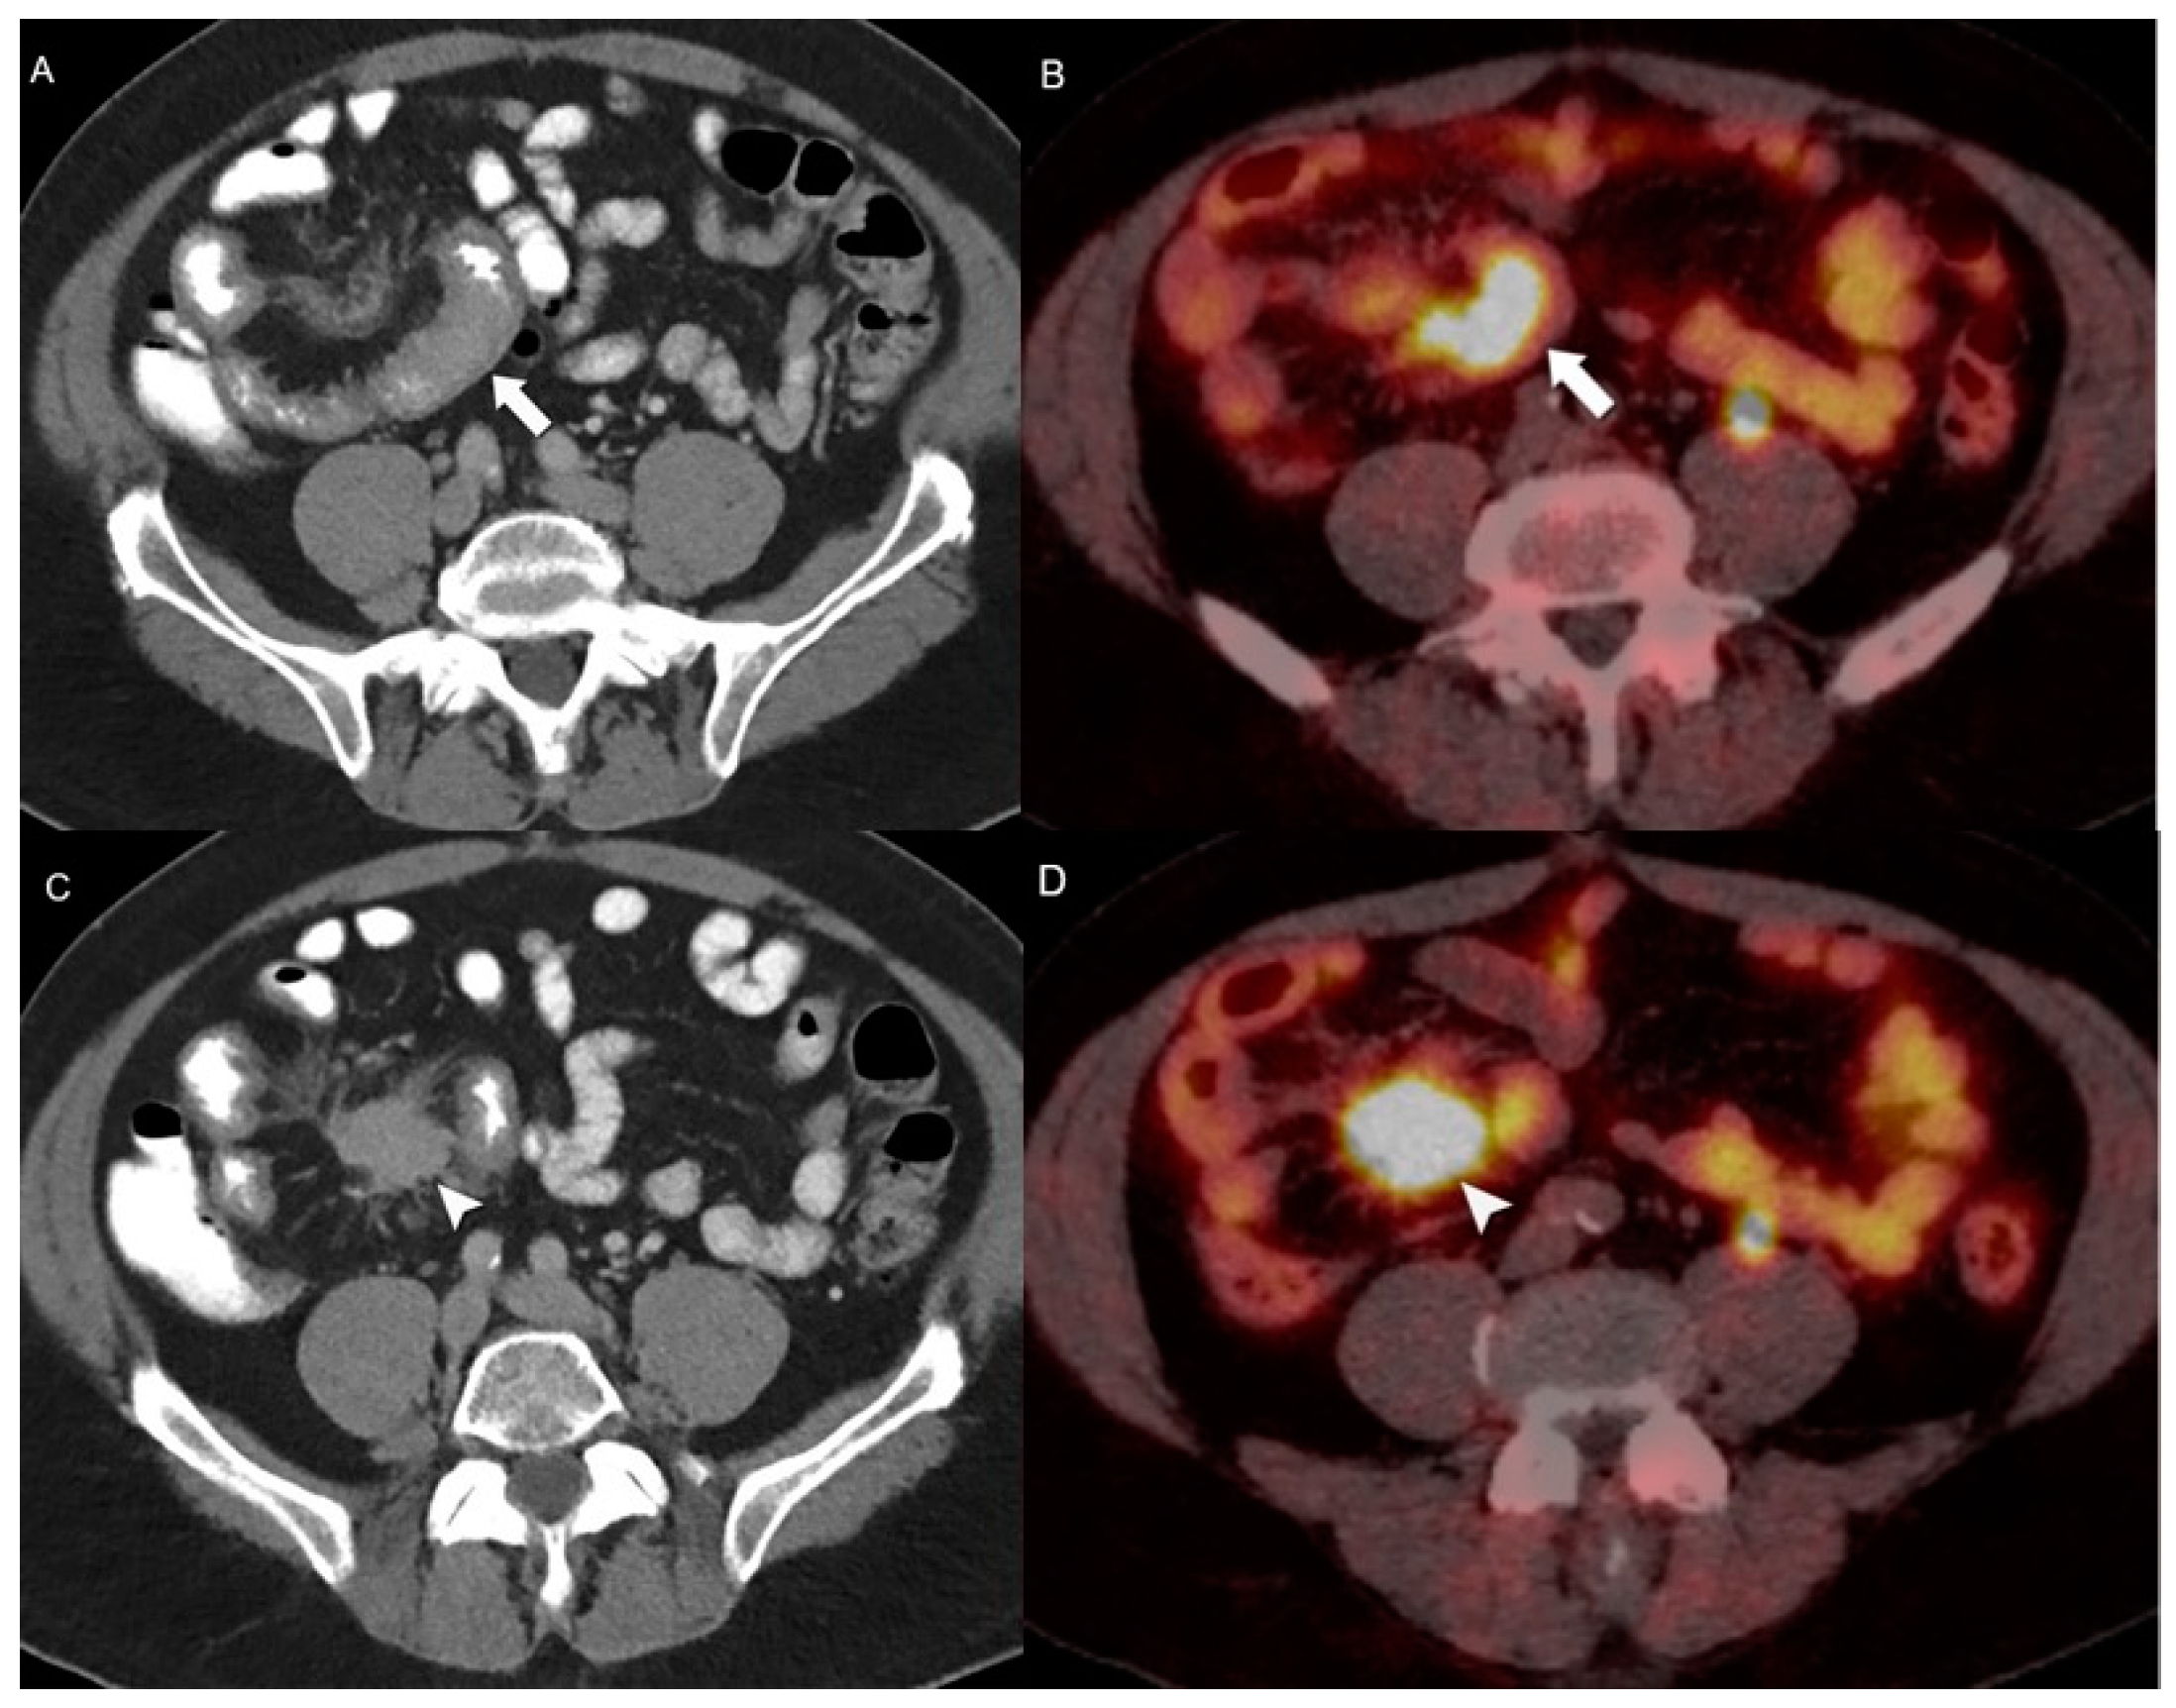

4.2. Hybrid Imaging of NENs